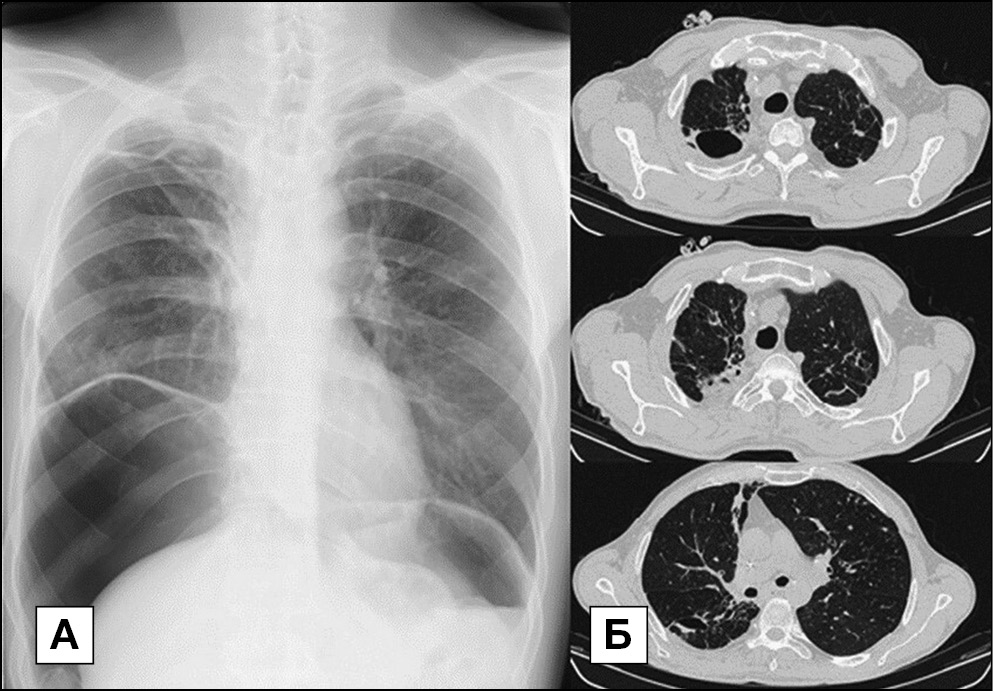

Рентгенографическое и компьютерно-томографическое исследование через 1,5 мес после операции: в динамике дальнейшее расправление правого легкого под пломбой. Дополнительных очагово-инфильтративных изменений в легких не выявлено (см. рис. 5).

Рис. 5. Рентгенографическое исследование от 04.07.16 и КТ органов грудной клетки от 22.06.2016 при выписке